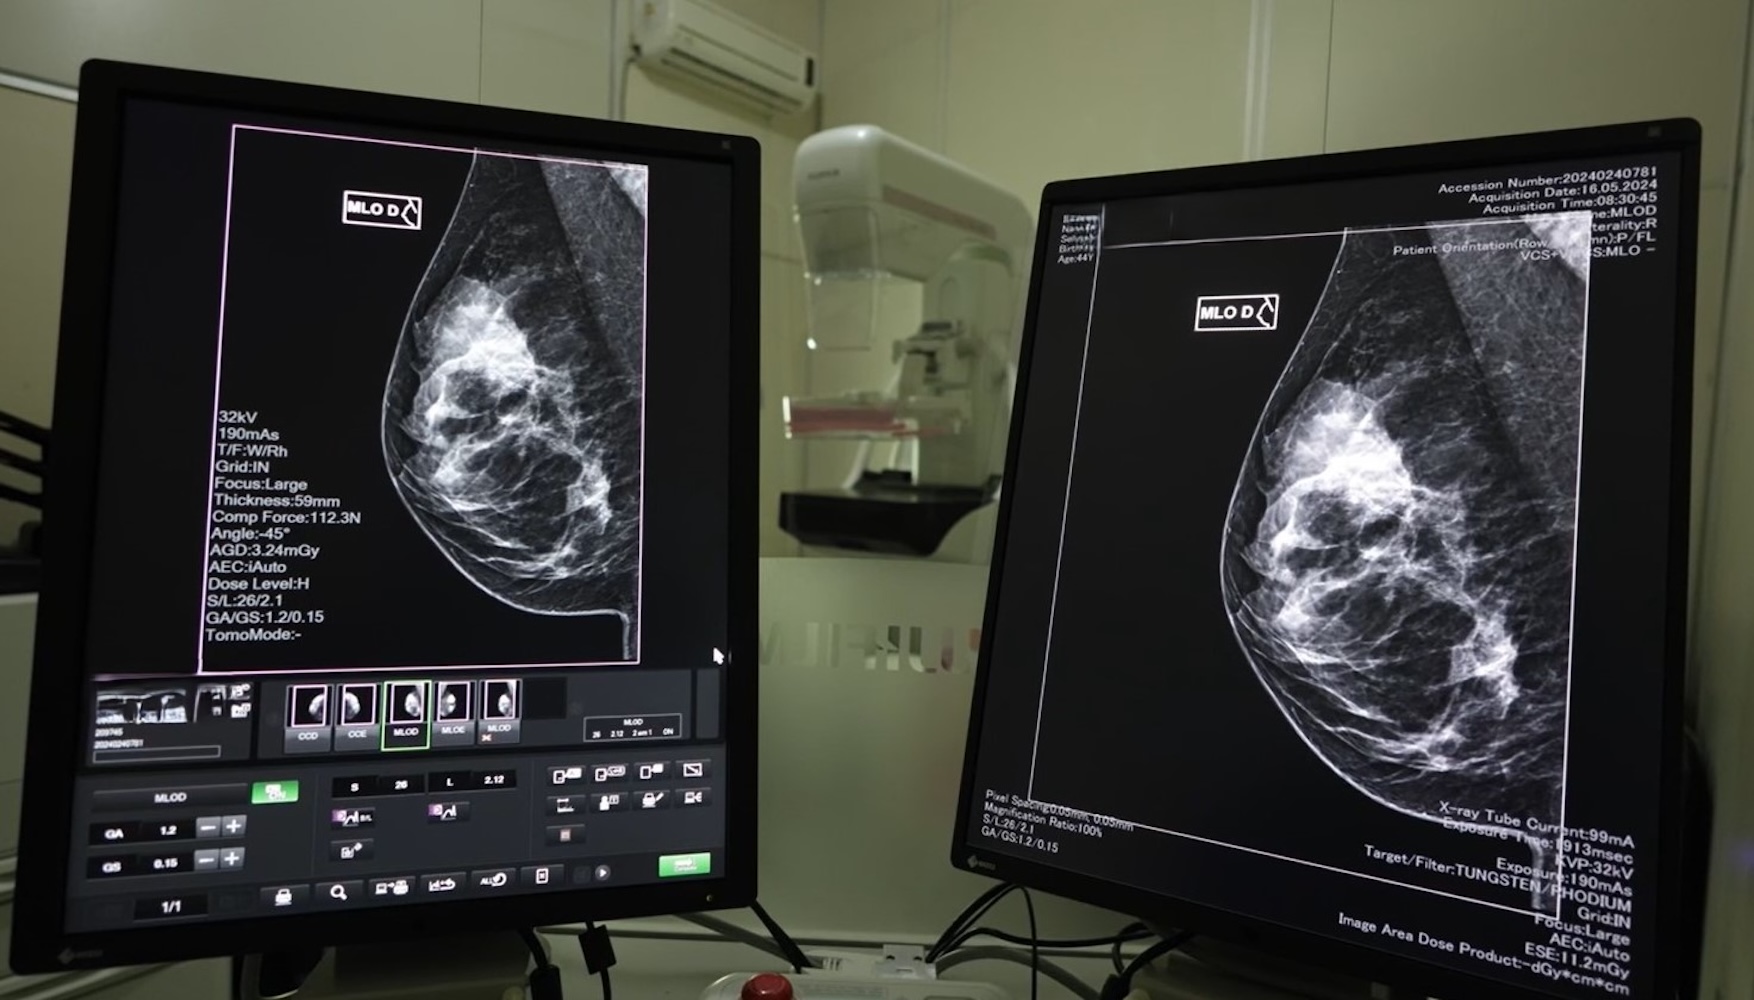

Leia maisPrevenção ao câncer de mama: mutirão de mamografias em SC busca reduzir fila de exames

Governo intensifica a luta contra o câncer de mama com mutirões e a ampliação da oferta de mamografias.